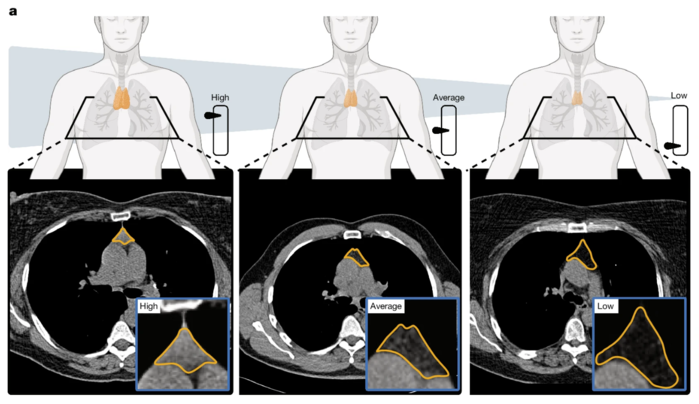

| ▲ a. 흉선 건강의 그림. 흉선 기능의 영상 기반 지표와 흉선 건강이 높음, 평균, 낮음인 세 명의 대표적인 사례를 보여준다. 흉선 부위는 주황색으로 표시되어 있다. (출처:Published: 18 March 2026 / Thymic health consequences in adults) |